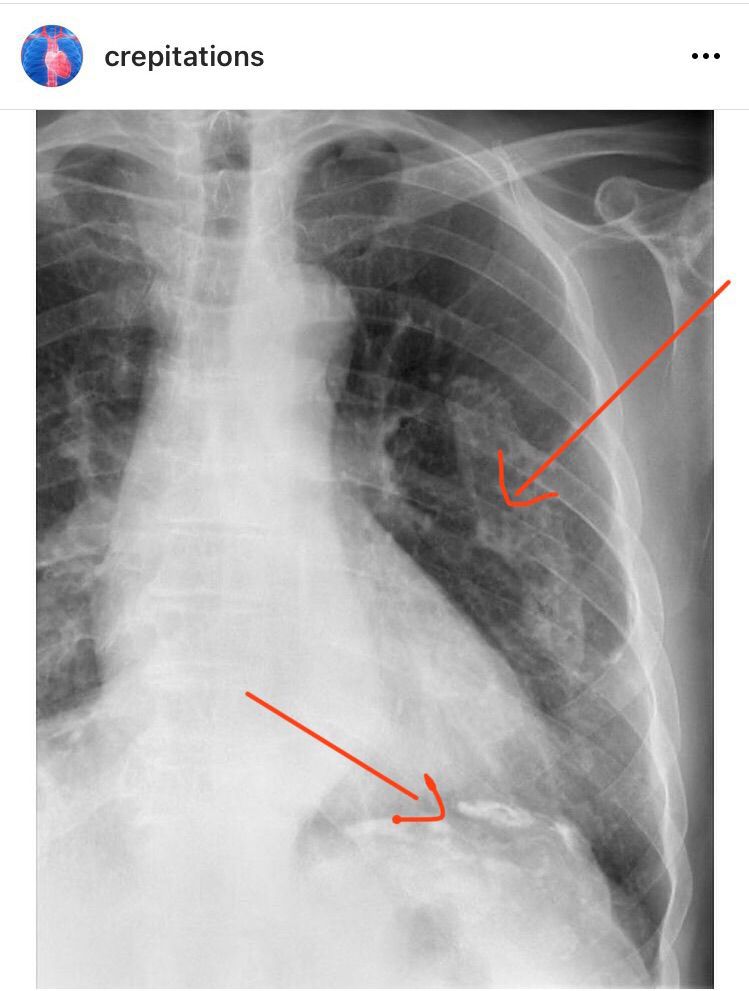

Asbestosis - Lung x ray

These are typical apperances of calcified pleural plaques secondary to asbestos exposure.